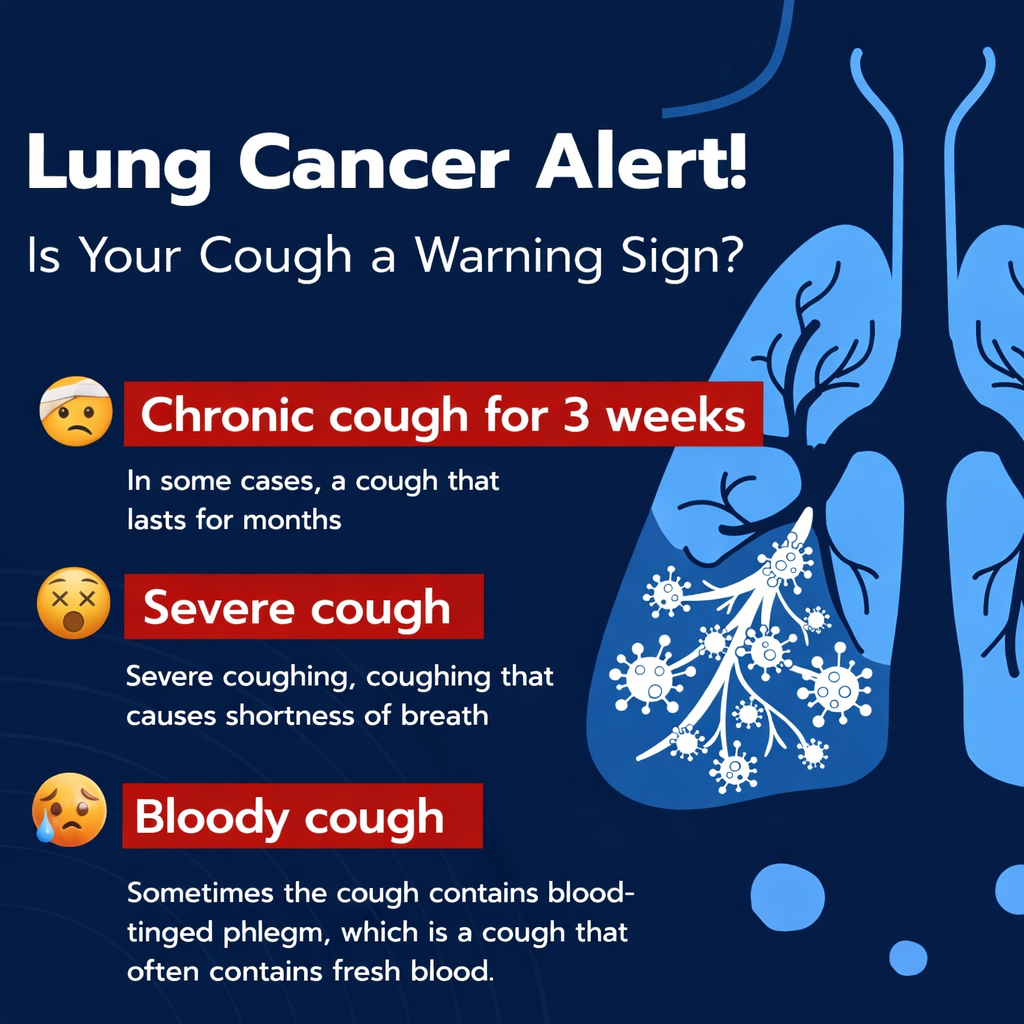

Persistent coughing or difficulty swallowing should also be treated as a warning sign. A persistent cough, hoarse voice, or chest pain could be a symptom of lung cancer or throat cancer. Difficulty swallowing food could be a symptom of cancer of the esophagus, throat, and other parts of the digestive tract. Change in bowel or bladder habits, such as constipation, diarrhea, or frequent urination, could be a symptom of cancer of the colon, rectum, or bladder.

Also, it is advisable to seek medical attention if you have long-lasting respiratory symptoms such as a persistent cough, hoarseness of the throat, and discomfort in the chest, especially if you are a smoker or have been exposed to harmful substances. Moreover, if you have a family history of cancer and have genetic risk factors, it is advisable to be even more careful and to regularly seek medical checkups and screenings even in the absence of symptoms.

Another real-life example of cancer is lung cancer, especially among smokers and people exposed to air pollutants. Some people suffering from lung cancer often underestimate the early stages of the disease, such as coughing and breathing difficulties, and think they are minor health complications. However, some people who seek early medical attention and early diagnosis through scans and other forms of early medical diagnosis are likely to receive effective treatment. On the other hand, some people suffering from lung cancer often demonstrate how cancer develops and advances to its late stages, especially when they seek medical attention too late.